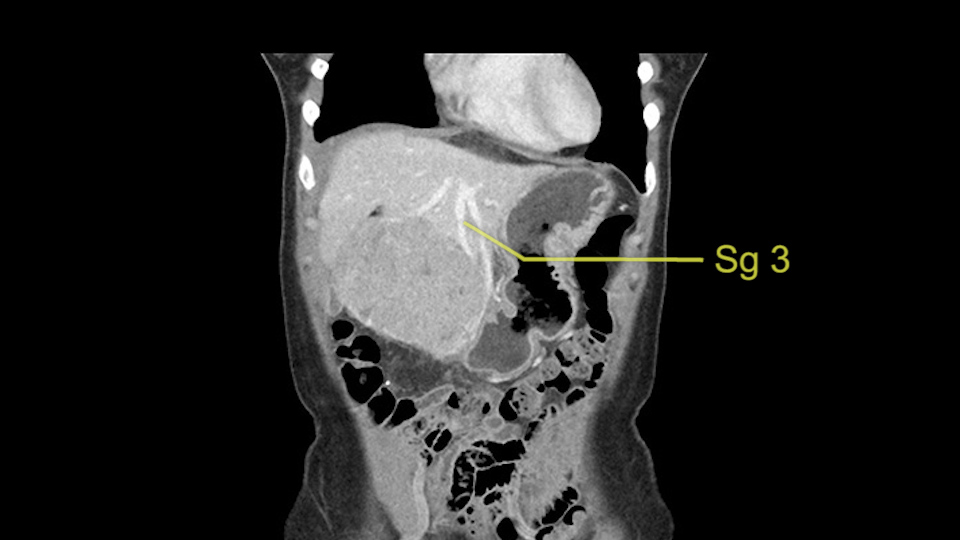

As I review the CT scan, we have both arterial and venous phases, the tumor is obvious. But I’ll start by saying that the liver itself does not appear to be cirrhotic to my eye. It’s got a normal contour and allied to that, that I do not see evidence of portal hypertension. The spleen is normal, there’s no collateral vessels. The tumor itself, I measured maximally at about 11 centimetres in diameter and I’m told the alpha fetoprotein is very high (over 10000), which is entirely consistent with this being a solitary hepatocellular carcinoma that is very exophytic. It seems to emanate off the inferior margin of Segment 3 (because that’s the falciform). I’ll start by saying that this is not transplantable. The tumor exceeds our guidelines for transplantation, but it's likely resectable based on normal liver and no portal hypertension.

So the issue with regards to resection. A left sided tumor. I believe I can see the falciform ligament right here so we’re looking at a resection of Segments 2, 3 of the left lobe of the liver. The left portal vein is right there. I think we’ll be wiser to take the left portal vein and therefore get well into Segment 4 and do a left hemihepatectomy. Certainly, one does not need to take the middle hepatic vein; it’s miles from the tumor.

The other thing I would do in this case is to certainly to assess the coronal phase as we can see in the coronal phase, this tumor looks like it's growing from Segment 3, and again I don’t think there’s involvement of the right side of the liver or even on Segment 4.

La decisión aquí, y otra vez mirando, me parce importante mirar a los cortes coronarios porque parece que este tumor cuelga del segmento tres y aquí la cuestión va a ser si vamos a realizar una resección más limitada y hacer una recesión del segmento tres, o si vamos a tener que realizar una hepatectomia izquierda. En cuanto a puntos importantes en ambas opciones, en todos los casos vamos a intentar realizar un recesión anatómica ya que hay datos en la literatura que parecen indicar que una resección anatómica tiene mejores resultados oncológicos comparado con una recesión no anatómica; entonces realizaremos una resección del segmento tres y en este caso trataremos de buscar el pedículo que va al segmento tres, en este caso probablemente sea una resección del segmento tres, realizare una maniobra de Pringle y clampare el hilio para evitar el sangrado.